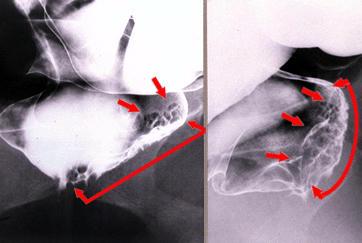

部位(臓器別)大腸/直腸

検査方法X-P

病変の最大径(ミリ)35〜40